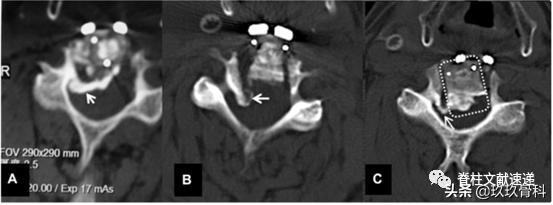

之前提到截骨槽足够宽才能保证ACAF的减压效果,如下图所示,普通开槽沿a虚线进行,遇到宽基底OPLL时须采用c线斜向外开槽才能实现彻底减压。但椎动脉在椎体外侧,开槽过宽椎动脉损伤的风险如何?这篇文献通过尸体和影像学研究进行了评估。

文章认为钩突尖可以作为开槽的解剖标志,开槽后距离横突孔约2mm距离。下图为尸体解剖图片,a开槽线位于钩突尖内侧,b横突孔内缘,c椎弓根内缘投影,神经钩紧贴椎弓根。

从解剖来说,ACAF不易损伤椎动脉,但考虑到解剖变异,术前行CTA检查是有帮助的。作者提出3条避免损伤椎动脉的技巧。1)避免使用粗钻头截骨开槽,2)术中保持中线,参照钩突尖部,3)术中随时探查截骨外壁的完整性,这一步尤其重要。